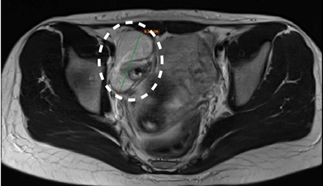

to a diagnosis of nephrotic syndrome. Renal biopsy was inconclusive1. Further evaluation, including abdominal

ultrasound and MRI, revealed a 7 cm mass in the right ovary with benign imaging

features (Figure 1). Elevated serum CA 19-9 levels were detected, while

Figure 1: Axial Magnetic

Resonance Imaging (MRI) reveals a well-defined ovarian mass in the right

adnexa, which is consistent with a mature ovarian teratoma. The lesion exhibits

benign imaging characteristics without evidence of invasion